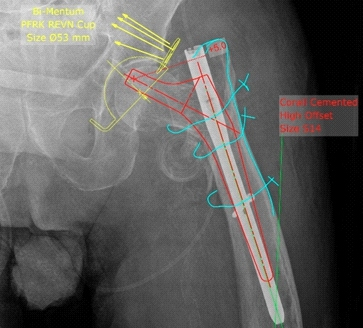

返修手术前规划:髋关节置换。